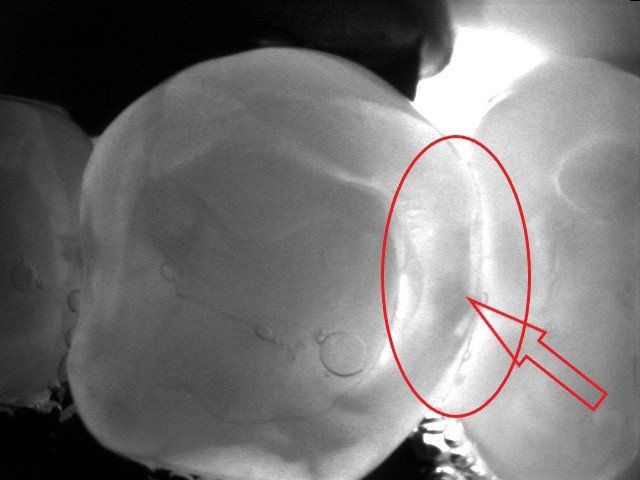

Viene presentato un caso in cui si evidenzia la presenza di carie mesiale e distale su un 25 (secondo premolare superiore di destra) attraverso l'analisi radiografica. Si deve sottolineare la difficoltà di metterne in risalto e di determinarne l'estensione solo mediante la radiografia. Nella fotografia successiva, l'entità e l'estensione della carie appaiono notevolmente superiori a quanto potesse essere dedotto dalla sola radiografia. Si mostra poi la cavità ripulita dalla carie, evidenziando la perdita di tessuto dentale causata da essa. Infine, si presenta l'otturazione appena completata, con i segni della cartina da articolazione ancora visibili, utilizzata per verificare l'altezza della cura, che richiederà successivamente un ulteriore rifinitura e lucidatura.

Un particolare utilizzo di due fasci laser e di un sensore che trasforma la transilluminazione in immagine visibile sul monitor del computer trova un utilizzo anche nella diagnosi della carie qualora l’immagine radiografica risulti dubbia o non dirimente di lesione cariosa. Ecco un esempio in cui radiologicamente si vede un’immagine non chiaramente rapportabile ad una carie come indicato dalle frecce nella radiografia a fianco. Con l’ausilio del laser si riesce ad evidenziarne completamente i limiti e la grandezza come visibile dalle due immagini e dalle frecce che indicano la carie. Tuttavia, per correttezza, va spiegato che l’efficacia di questa indagine può essere effettuata solo in determinate circostanze cliniche e che le radiografie risultano sempre necessarie.